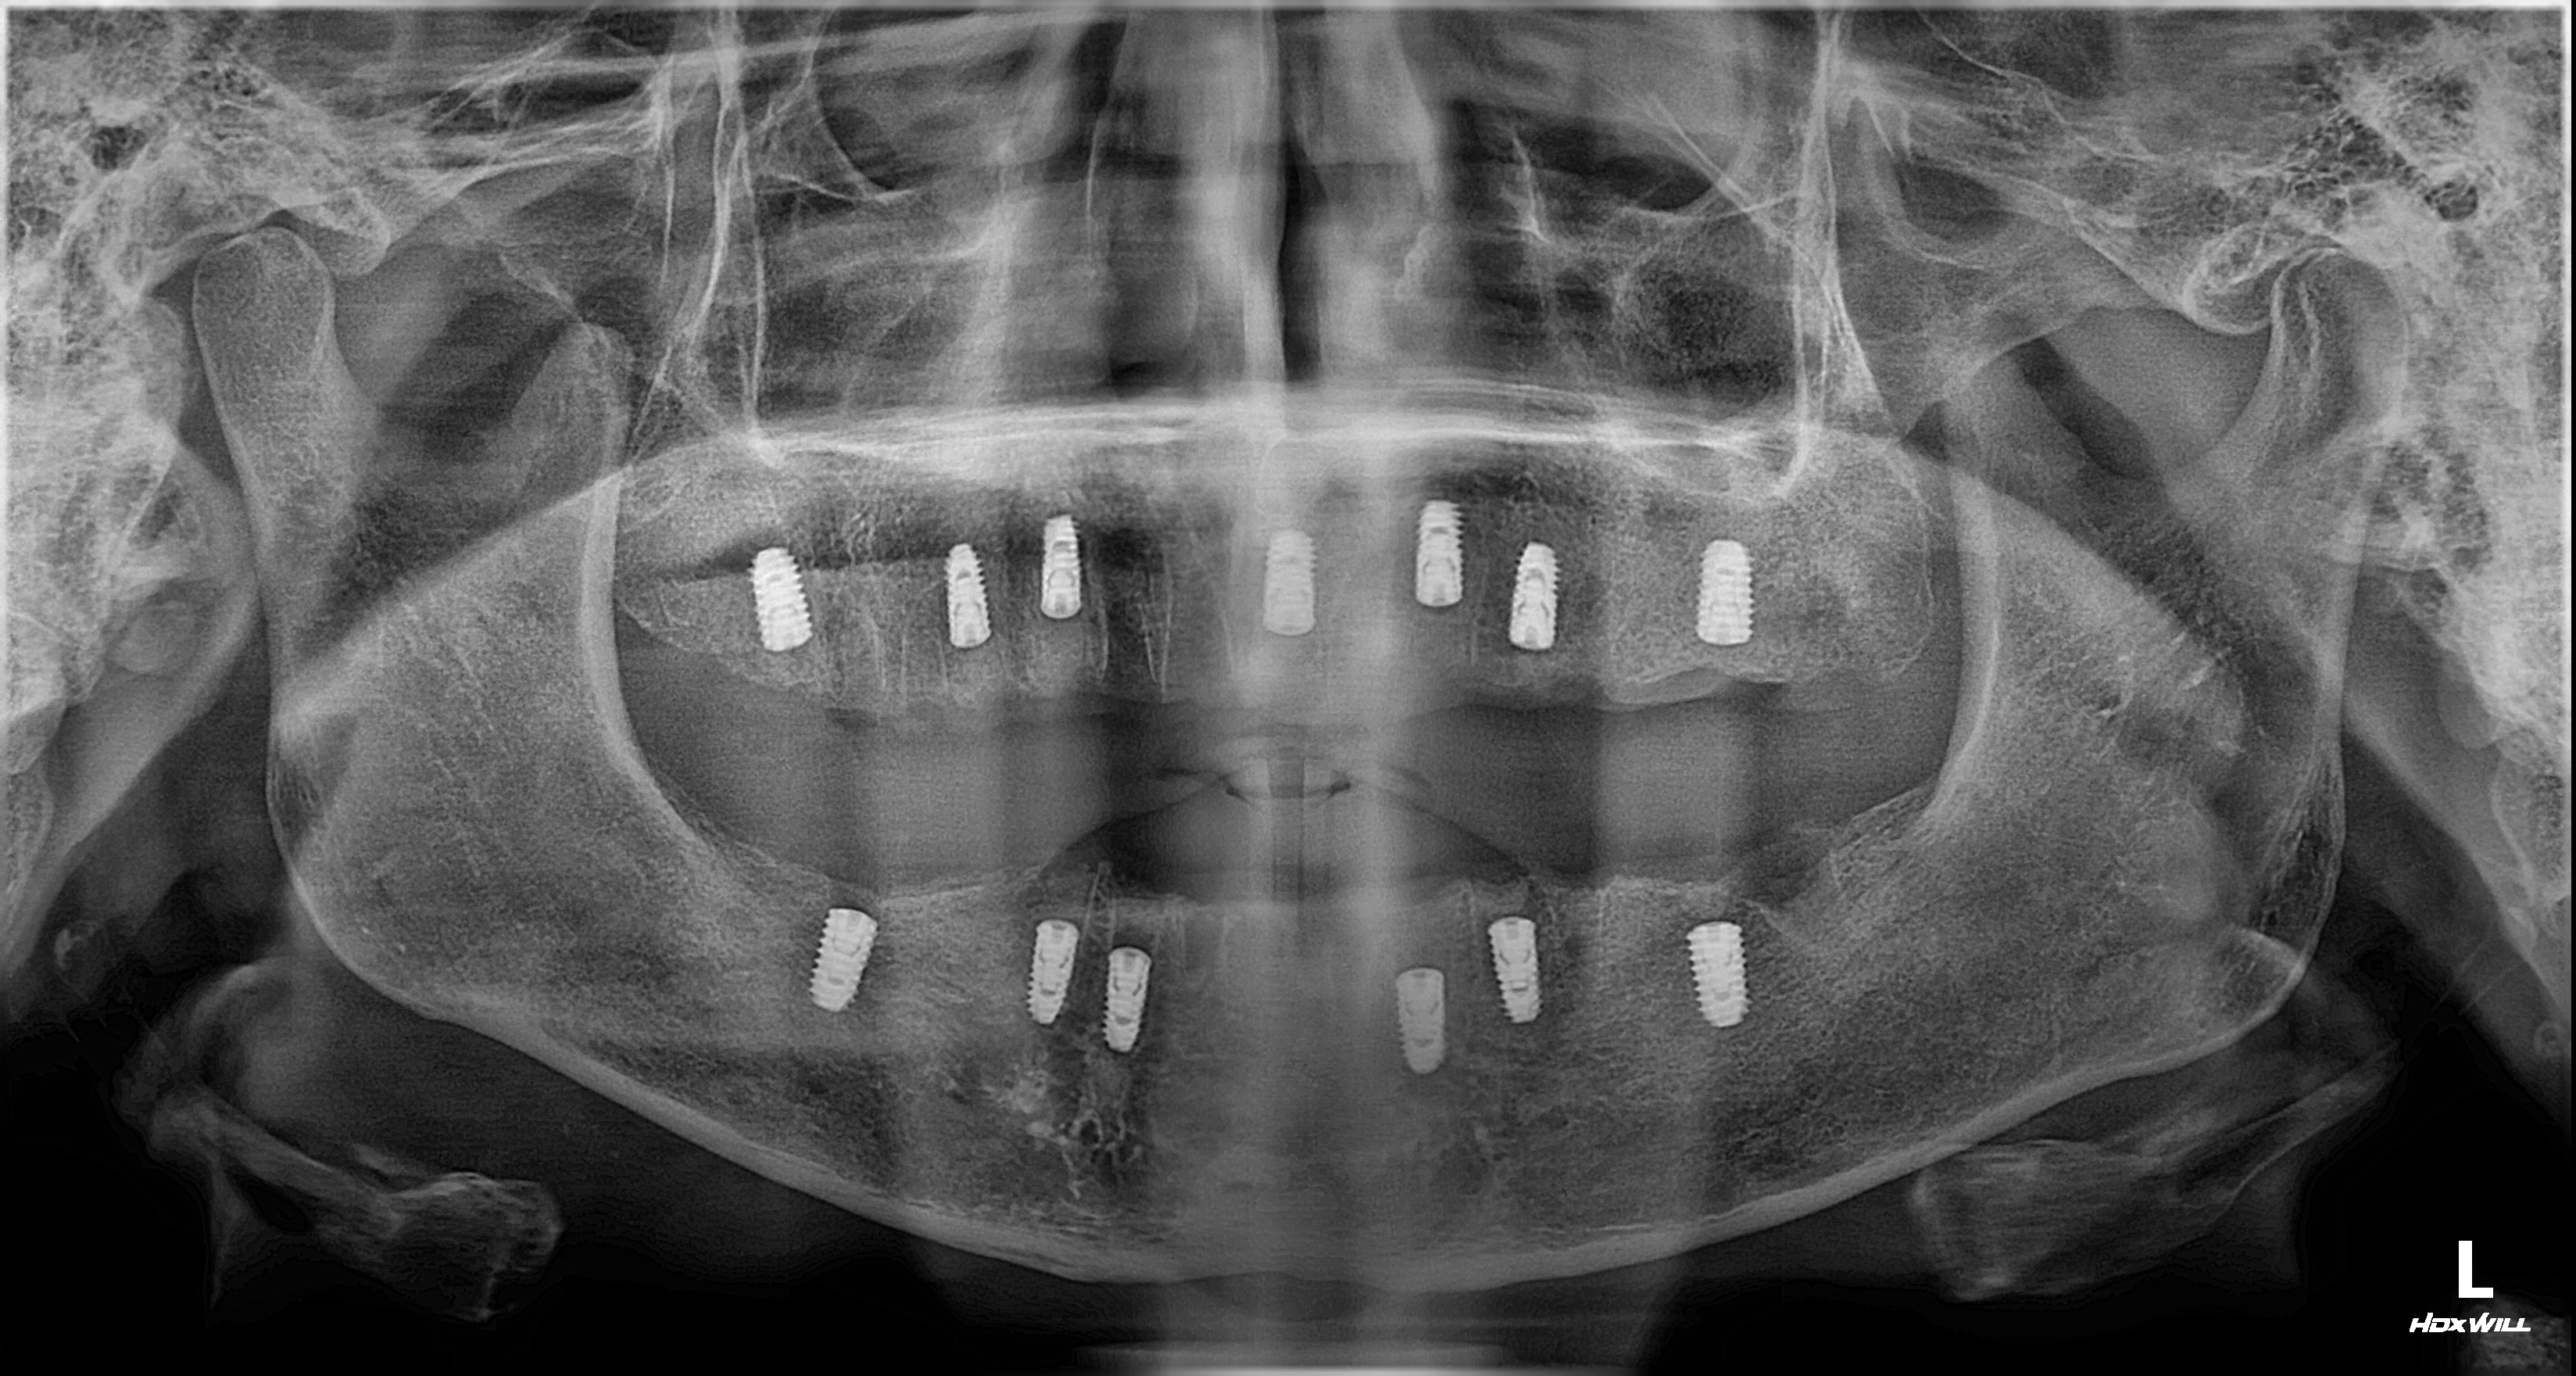

촬영일시: 2025.05.27

촬영일시: 2025.10.01 [ 치료기간: 2025년 05월 27일 ~2025년 10월 01일 ] ※ 365서울앞선치과의원의 모든 컬럼은 각 진료과 의료진이 직접 작성합니다. 365서울앞선치과의원 임상 케이스 게시물은 환자분께 의학적으로 정확하고 상세한 정보를 드리기 위해 각 진료과 의료진이 직접 작성하며, 모든 증례 사진은 본원 의료진이 직접 시술한 증례를 촬영한 것으로, 의료법 제23조, 제56조에 의거하며 환자분의 동의를 얻어 포스팅에 사용하였습니다. 또한 해당 케이스는 본 환자분의 치료 결과이며, 환자 상태에 따라 치료의 결과는 달라질 수 있습니다. |